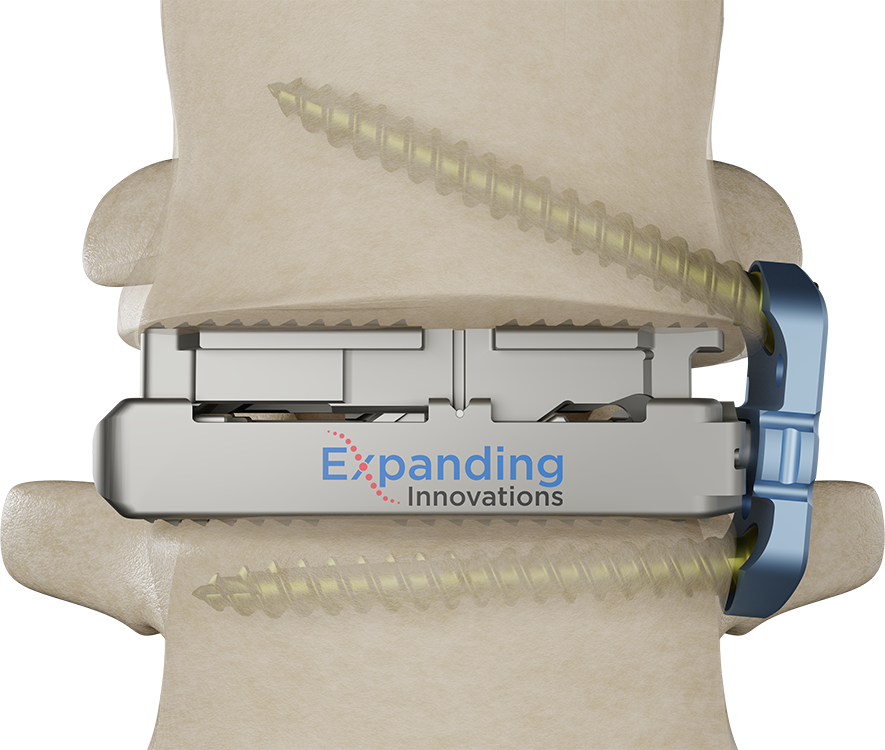

Modular Plating for Expandable Cage Technologies

Optional Attachment to X-PAC® LLIF Expandable Cages

Anatomical Conformity Without Compromising the Cage

A polyaxial connection allows plates to conform to the lateral anatomy without compromising the interbody. Variable Depth Capture provides the ability to connect to interbodies inserted beyond the cortical rim.